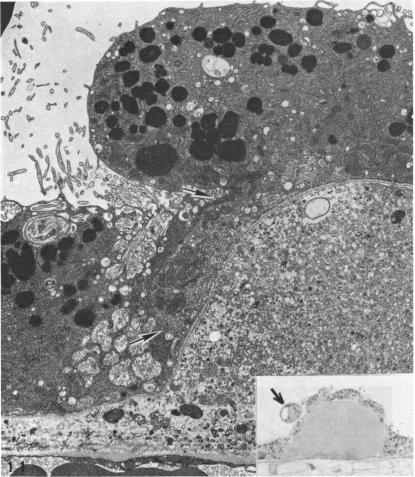

The ultrastructure of drusen.

Am J Ophthalmol. 1971 Jun;71(6):1196-205. doi: 10.1016/0002-9394(71)90963-9.